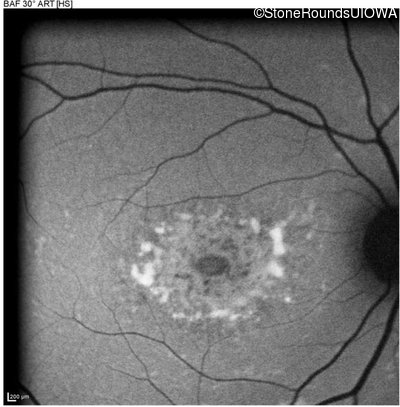

Age at visit: 22 years

Age at visit: 17 years

Age at visit: 18 years

Age at visit: 19 years